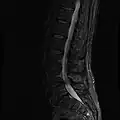

MRI